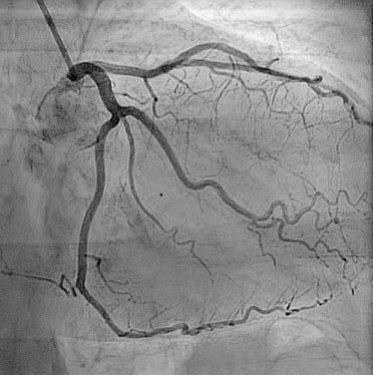

एंजिओग्राफी

एंजिओग्राफी ही एक वैद्यकीय इमेजिंग प्रक्रिया आहे ज्याद्वारे रक्तवाहिन्या आतून तपासल्या जातात. यामध्ये प्रामुख्याने धमनी आणि हृदयाच्या कक्षांची तपासणी केली जाते. या प्रक्रियेमध्ये रक्तवाहिन्यांमध्ये एक विशेष द्रव्य (कॉन्ट्रास्ट एजंट) इंजेक्ट करून, एक्स-रेच्या मदतीने चित्रण केले जाते.

एंजिओग्राफी का करतात?

- निदान: रक्तवाहिन्यांमध्ये अडथळे, अरुंद झालेल्या धमनी किंवा धमनीमध्ये मोठ्या प्रमाणात सूज (ॲन्युरिझम) आढळल्यास त्यांचे कारण समजण्यासाठी.

- डॉक्टरांना समस्येचे योग्य निदान करून सर्वोत्तम उपचार पद्धती ठरवण्यासाठी मदत करते.

- कार्डिओलॉजिस्टला रक्तवाहिन्यांमधून योग्यरित्या मार्गदर्शन करून संभाव्य धोक्यांपासून वाचवण्यासाठी मदत करते.

- तुमची स्थिती कशी प्रगती करत आहे आणि उपचार किती प्रभावी आहेत हे तपासण्यासाठी मदत होते.

- रक्तवाहिन्यांचे आजार समजून घेण्यासाठी आणि नवीन उपचारांची चाचणी घेण्यासाठी महत्त्वपूर्ण.